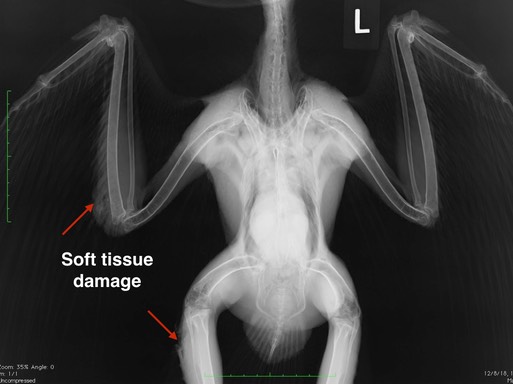

Red-tailed Hawk 18-737

An adult, female Red-tailed Hawk, also in excellent physical condition, was the second gunshot victim of the week. She was found a few miles south of Pendleton in a wheat field. She has wounds in her right leg and right wing consistent with a gunshot injury. The projectile did not break any bones, but it caused significant damage in the muscles of the leg and wing. To make matters worse, the hawk’s blood lead level is 19.8 micrograms/deciliter, a toxic amount of lead. In addition to treating the infection related to the gunshot wounds, we will also need to chelate her to remove the lead.